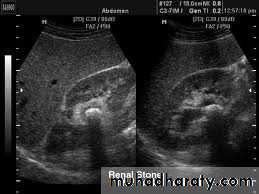

Ultrasound findings

1-Dilatation of the P.C.S. appears as multilocular fluid collection within central echo complex.

-With more severe distention, dilated calyces appear as

Multiple cysts but communicating with each other unlike true cysts.

2-Stones larger than 5mm are easily seen on US but smaller ones may be missed.

-They produce intense echoes (hyperechoic) and cast acoustic shadows.

-Proximal and distal ureteric dilatation can be easily identified unlike mid-ureteric dilatation, and stones located in the middle third of the ureter are hard to be demonstrated unlike upper and lower ureteric stones (especially those lodged in the vesico-ureteric junction or pelvi -ureteric junction) which are easily identified by ultrasound.